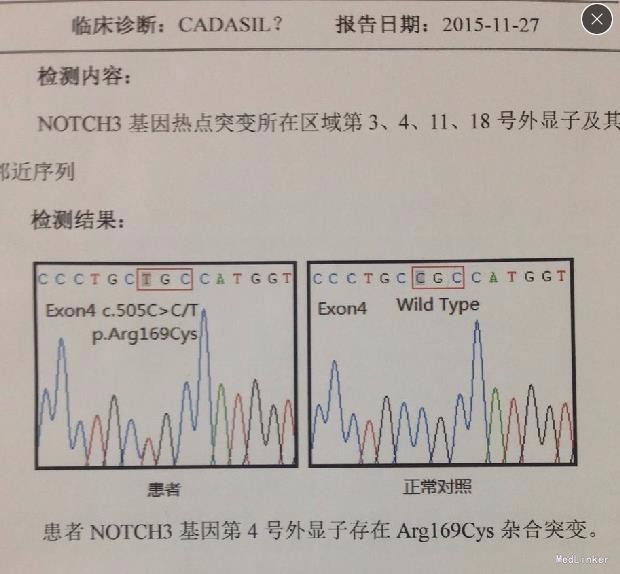

神清,说话吐词清晰。双侧瞳孔等大等圆,眼球运动正常,光反射灵敏,无面舌瘫,颈软。左手握力下降,右下肢轻瘫试验阳性,双上肢腱反射稍高,双侧膝反射亢进,霍夫曼征及内罗里索征阳性。直线行走试验阳性,闭目难立征阴性,双侧指鼻试验阴性。双侧病理征未引出,四肢浅感觉等称。实验室检查未见明显异常。MRI示:脑干、双侧颞极、外囊、额顶叶、放射冠区及丘脑、脑桥异常信号,结合MRS提示符合缺血性改变,部分软化灶形成.结合病变位置(颞极、外囊)及患者年龄,考虑CADASIL可能。头颈血管大致正常,NOTCH3基因见图

诊断:CADASIL?按常规脑梗塞治疗。

CADASIL是常染色体显性遗传病,伴有皮质下梗死和白质脑病的常染色体显性遗传性脑动脉病是一种遗传性小动脉疾病,位于19号染色体上的Notch3基因突变所致的遗传性脑小血管疾病,表现为皮质下缺血事件,并导致进行性痴呆伴假性球麻痹。治疗方面目前没有特殊治疗,无法阻止病情进展